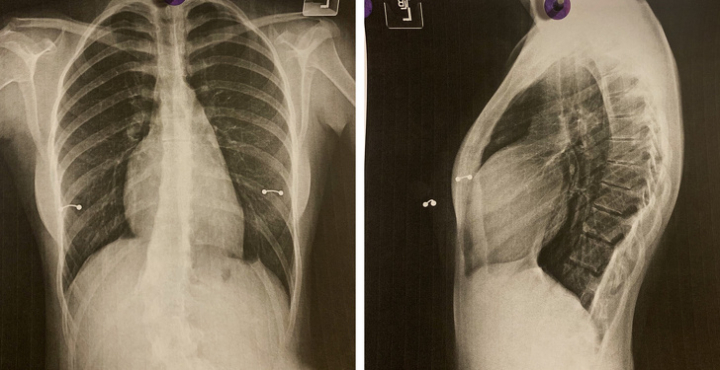

12. «Мне сделали рентген грудной клетки перед операцией, и думаю, что этим стоит поделиться»